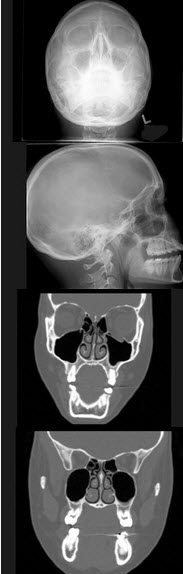

25岁女性,车祸伤及面部,X线及CT检查如图所示,下列哪些描述或诊断正确()

A、X线示左侧眶底较正常变低

B、CT发现左侧眶底骨质断裂

C、左侧上颌窦内见气-液面

D、考虑为左侧眶底骨折

E、左侧上颌窦积液

A,B,C,D,E